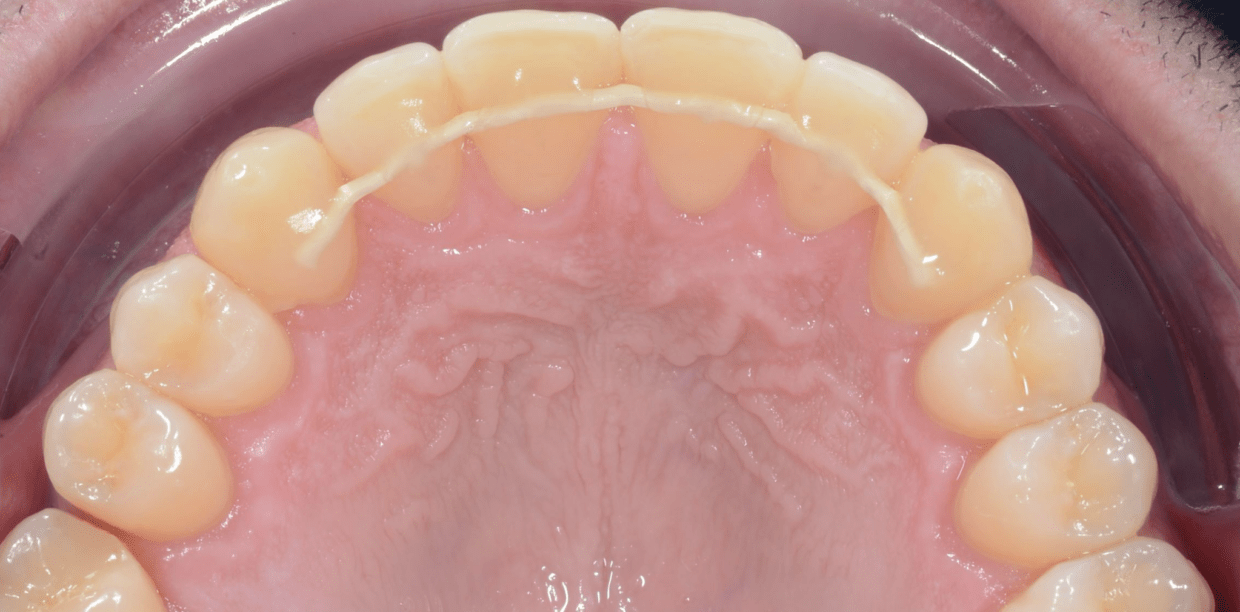

Cas cliniques

Simple - White

Simple - White

Simple - White

Simple - White

Simple - White

Simple - White

Simple - White

Simple - White

Simple - White

Simple - White

Simple - White

Simple - White

Simple - White

Simple - White

Simple - White

Simple - White